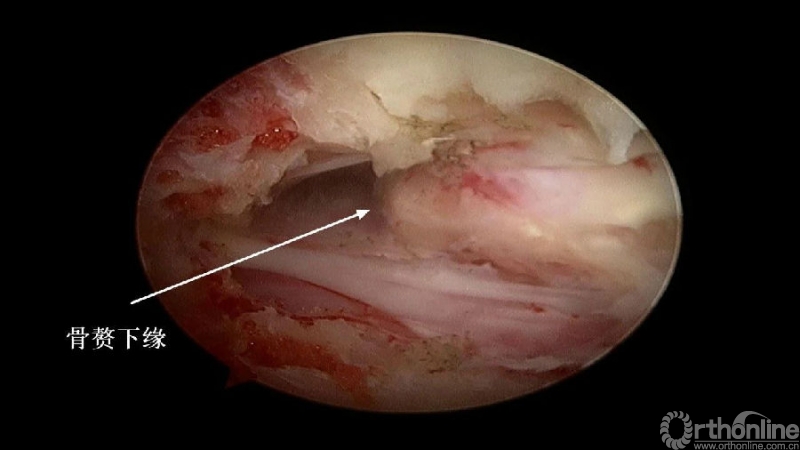

2.显露骨赘的内侧面及上下缘;

2. 术中骨赘的界限?